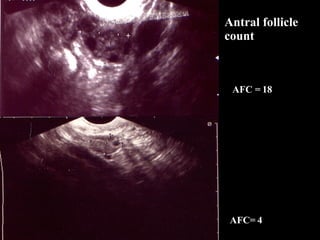

Antral follicle count Cycle day Follicle size <  3 – diminished reserve Evaluation of the Ovary Testing of Ovarian Reserve

Antral follicle count AFC = 18 AFC= 4

Antral follicle countCycle day Follicle size < 3 – diminished reserve Evaluation of the Ovary Testing of Ovarian Reserve

Antral follicle countAFC = 18 AFC= 4